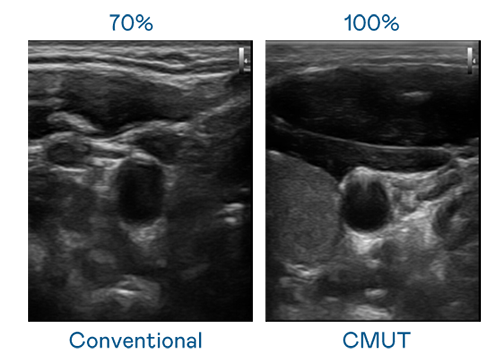

CMUT 技术是一种用电容式微机电元件来产生超音波讯号的技术。与传统 PZT 压电式技术相比,CMUT 频宽增加 30%,更宽频的超音波讯号让影像解析度大幅提升,是实现高影像品质医疗超音波扫描、促进精准医疗发展的关键技术。

大频宽带来超清晰影像

超音波影像的解析度高低,首先取决于探头能发出的讯号频宽。BB电子 CMUT 可提供高清晰的超音波讯号,提供高频宽、高灵敏度、影像纹理细节更高的超音波影像,协助医护人员缩短影像判读时间及利用精准的医疗影像进行诊断。